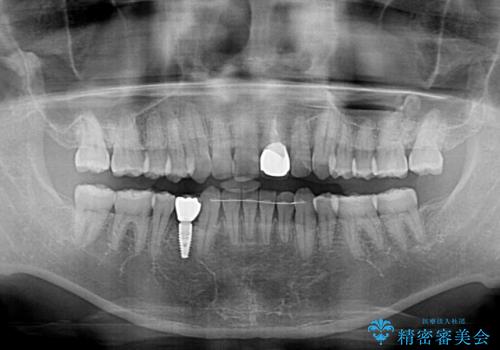

咬合力が強く、インビザラインのみではディープバイトを改善することができず、半年間ほどワイヤー装置による矯正治療を行いました。

インプラントの埋入は矯正治療中に行い、矯正治療後はインプラント上補綴および、前歯のセラミック治療を行いました。